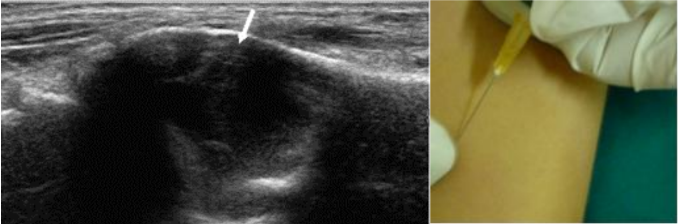

Hình minh họa: Kỹ thuật chọc hút tế bào xương bằng kim nhỏ dưới hướng dẫn siêu âm

(Được thực hiện trong phòng siêu âm vô trùng tại khoa cơ xương khớp bệnh viện Bạch Mai)